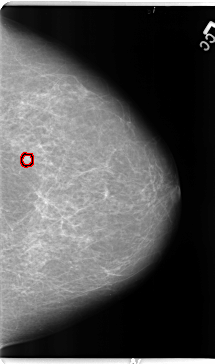

Digital Database for Screening Mammography

Volume: benign_04 Case: B-3155-1

B_3155_1.RIGHT_MLO

B_3155_1.RIGHT_CC

FILE: B_3155_1.LEFT_CC.OVERLAY

TOTAL_ABNORMALITIES 1

ABNORMALITY 1

LESION_TYPE MASS SHAPE OVAL MARGINS ILL_DEFINED

ASSESSMENT 4

SUBTLETY 4

PATHOLOGY BENIGN

TOTAL_OUTLINES 1